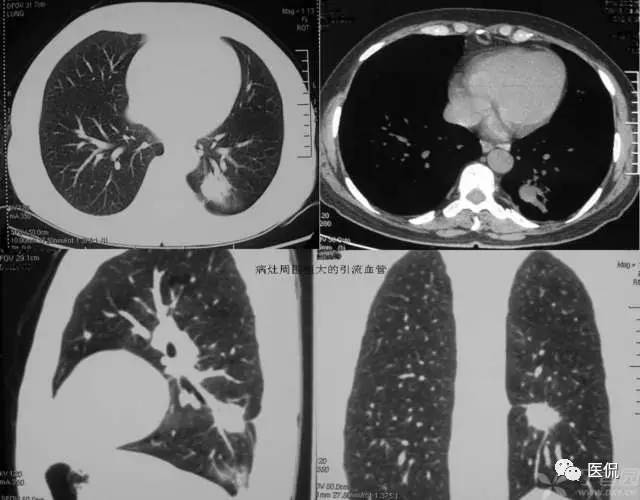

血管集束征的形成是由于肿瘤组织向血管支气管鞘或小叶间隔生长,瘤体内纤维组织增生或瘢痕形成,牵拉临近血管向瘤体集中所致。其中进肺门侧的血管束、支气管构成,血管壁多为扩张的小动脉,说明肺癌供血丰富;远肺门侧的血管束由扩张的小静脉组成,可能和静脉回流受阻有关。血管集束征的形成机制是由于恶性肿瘤细胞产生肿瘤生成因子诱发肿瘤形成新生血管,尤其是血供丰富的恶性肿瘤,由于其生长活跃,常致使肿瘤供血的血管代偿性增粗,这些血管长扩张或伴有肿瘤细胞的支气管动脉鞘浸润或瘤栓形成。这就意味着,肿瘤或结节周围血管是否增粗表明该病变的良恶性程度。血管集束征的出现与肿瘤或结节的大小有关,小于1公分的病灶较少出现;腺癌出现的的几率较高,因为腺癌供血丰富,纤维化形成的更明显。尤其要注意的是,一支血管引向结节或肿瘤内,不只仅见于恶性结节,也可见于良性病变如结核球、炎性假瘤或错构瘤。对于引向两性结节的这支血管可看作血管连接,而不是血管集束征。多支血管引向病变即出现了血管集束征这在恶性肿瘤出现的机会较高。此外,肺恶性结节累计静脉的机会更多,病灶不论大小,如果见到结节累及静脉,强烈提示恶性可能。判断某支血管是动脉还是静脉,主要根据其走形来判断,动脉主要和支气管伴行,静脉主要位于病灶的边缘绕行。关于血管集束征的血管,有学者认为大多数并非肿瘤供血血管或肿瘤血管,被肺癌卷入的肺动脉不参与肿瘤供血。另外,肺癌瘢痕的形成和癌巢的增殖与破坏与血管集束征和胸膜凹陷征的形成有关。血管集束征主要见于肺癌,尤其是腺癌和肺泡细胞癌。但是该征像不仅见于恶性肺结节,肺良性病变如结核球、球形肺炎等也可见到。所以仅根据血管集束征判断病变的良恶性并不是完全可靠的。

腺癌粗大的引流血管: